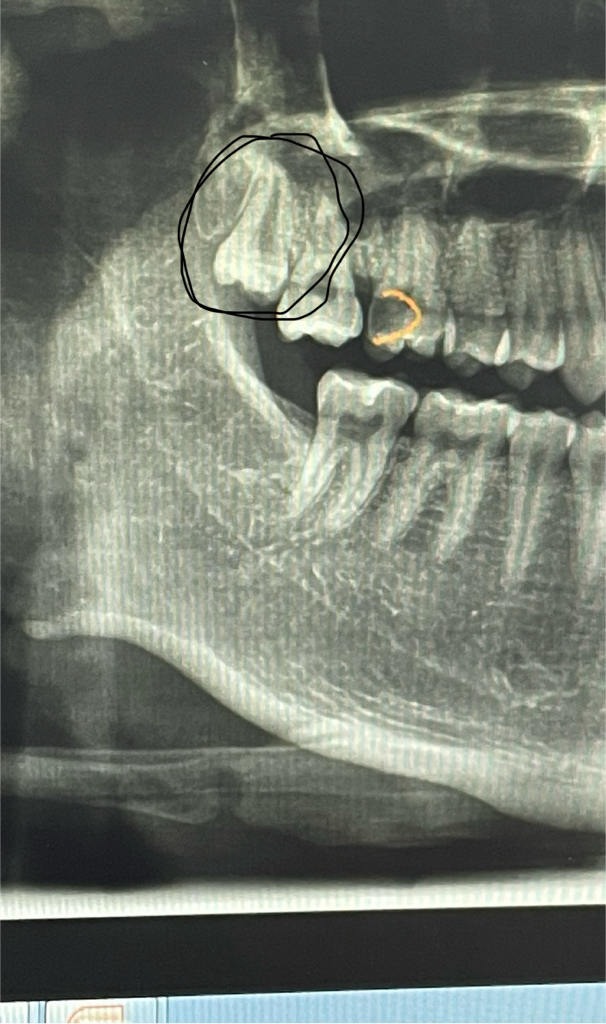

이거 매복 사랑니인가요?? 사랑니 발치할때 잇몸을 절개한후 발치해야하나요?

매복 사랑니인지 궁금합니다

발치할 때 잇몸을 절개하고 이를 잘라서 발치해야하나요??

잇몸 절개하지않고 한번에 뽑을 수 있는 치아인지도 궁금합니다

사진으로만 봤을 경우에는 매복 사랑니거나 부분적으로 맹출 되었을 수 있습니다.

발치에 난이도는 높지 않은 것으로 생각 됩니다.

매복사랑니로 절개를 하고 발치를 해야합니다. 절개를 하더라도 크게 통증이 심한 것은 아닙니다.

상악은 보통 절개까지 하지는 않는 경우도 있지만 기구접근이 어렵다면 절개하고 하는편이 수월합니다 그렇게 어려운 케이스는 아닐것으로 판단됩니다

저정도면 잇몸에 살짝 매복된상태인거 같습니다. 치아가 맹출이 어느정도 됫다면 잇몸절개 없어도 발치가 가능할수 있을것같습니다.